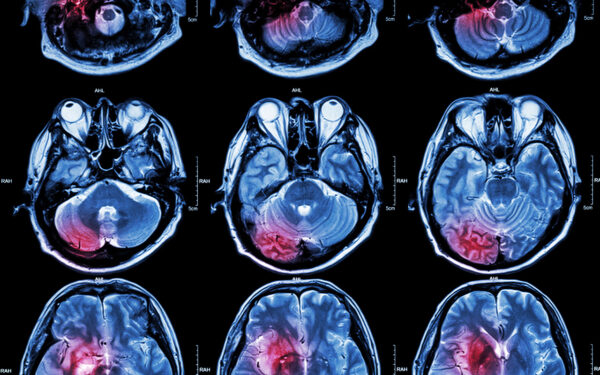

Training for medical imaging technologists and repair technicians should grow in coming years to mirror the expected growth of the global medical imaging market. Grand View Research is one research firm that excepts the global medical imaging market to continue its recent growth in the coming years.

“The global medical imaging market size was estimated at $39.8 billion in 2023 and is projected to grow at a CAGR of 4.9% from 2024 to 2030. The increasing prevalence of chronic diseases, demand for early disease diagnosis and detection tools, along with growing geriatric population are anticipated to drive this growth. Factors such as the rising investments by key players, product innovations, and technological advancements such as integration of artificial intelligence (AI) in medical imaging and development of point-of-care medical imaging equipment are expected to further fuel the growth,” according to Grand View Research.

New technology is one area that Grand View Research predicts will fuel growth of the global medical imaging market. New technology also means additional training for imaging professionals.